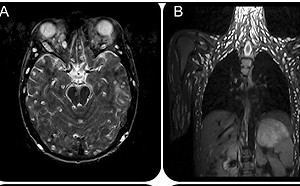

吃生豬肉抽蓄「感官扭曲」!男子就醫檢查驚見「全身長滿寄生蟲」